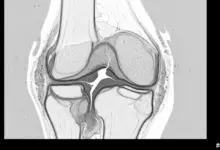

Os exames de imagem entram para complementar a avaliação. Radiografias ajudam a mostrar redução do espaço articular, desvio de eixo e sinais de artrose.

A ressonância magnética tem papel importante na análise da cartilagem, do osso subcondral, dos meniscos e dos ligamentos, com utilidade especial nas fases mais iniciais da degeneração.